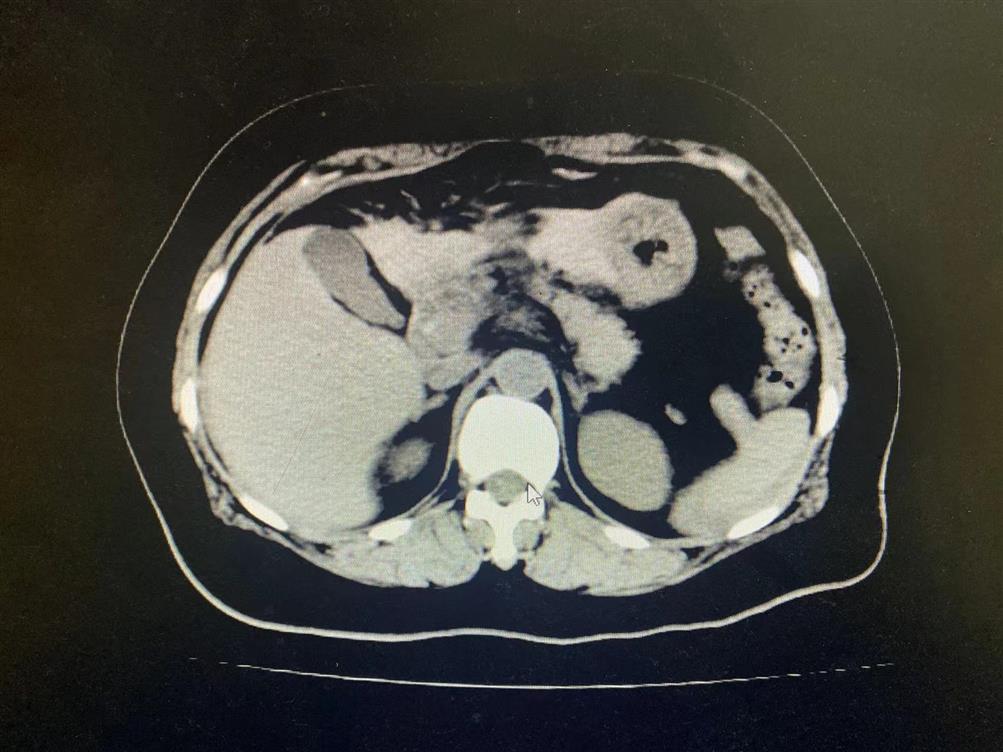

11月27日上午,吴女士(女,53岁)发生车祸,导致腹痛剧烈伴恶心呕吐、心慌胸闷。我院“120”急诊接入外一科抢救治疗,经腹部CT检查提示肝脏挫伤、胃及十二指肠挫伤、腹腔内出血。

在手术中发现患者肝十二指肠韧带破裂、肝右叶(八段)挫伤伴血肿、胰头挫伤伴血肿、十二指肠挫伤伴血肿、腹膜后血肿、胃壁挫伤伴血肿、网膜挫伤、上腹壁挫伤。术中肝十二指肠韧带撕裂伤伴活动性出血,随给予肝十二指肠韧带修补,手术顺利完成。患者返回重症监护室,医护人员继续严密监测各项指标。目前生命体征稳定、患者神志清楚,各项指标明显好转并已转出重症监护室。